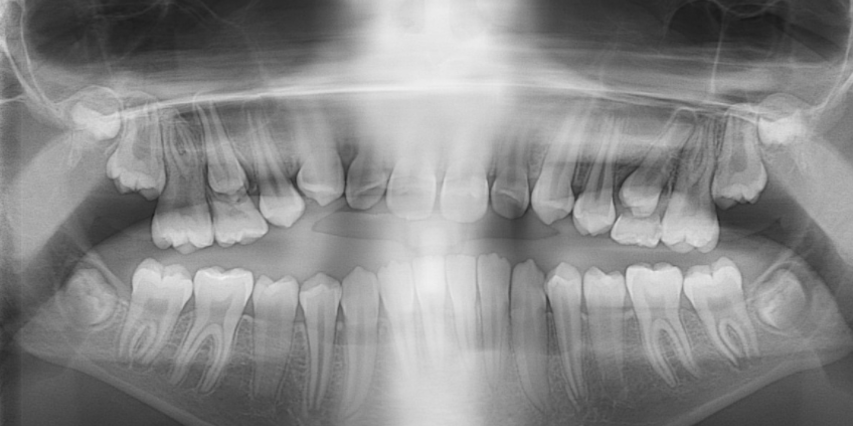

Llama la atención a primera vista la mordida abierta bilateral, especialmente pronunciada entre el cuadrante 1 y 4 debido a una interposición lingual en posición estática. Entre otros hallazgos fundamentales, observamos: un patrón dolicofacial severo (VERT: -2), una compresión de la arcada superior que cursa con un perfil y relación oclusal de clase III y la rotación del 35 y 45. Este caso se trató con un disyuntor, exodoncias de 44 y 34, brackets convencionales y educadores para rehabilitación de la lengua en un tiempo de 22 meses. Aunque estoy satisfecho con el resultado final, me hubiera gustado clavar la interscuspidación de premolares en el cuadrante I y IV, y mejorar la relación oclusal de cuadrante II y III. Sin embargo, lo bonito, es que hay a veces, en la ortodoncia real, que el paciente está satisfecho y quiere terminar antes de tiempo, o por el contrario, que el profesional intenta pero no consigue el resultado deseado. Y a mí más que compartir casos perfectos, me gusta mostrar mis errores, mi realidad.

-PASO A: Cita previa a la colocación de los arcos de acero redondos de 0,16: realización de ortopantomografía. Apuntar en una hoja clínica: paralelismo radicular ( ¿hay alguna raíz que no sigue dicho paralelismo?); posibles espacios residuales; pequeñas rotaciones de dientes ;etcétera.